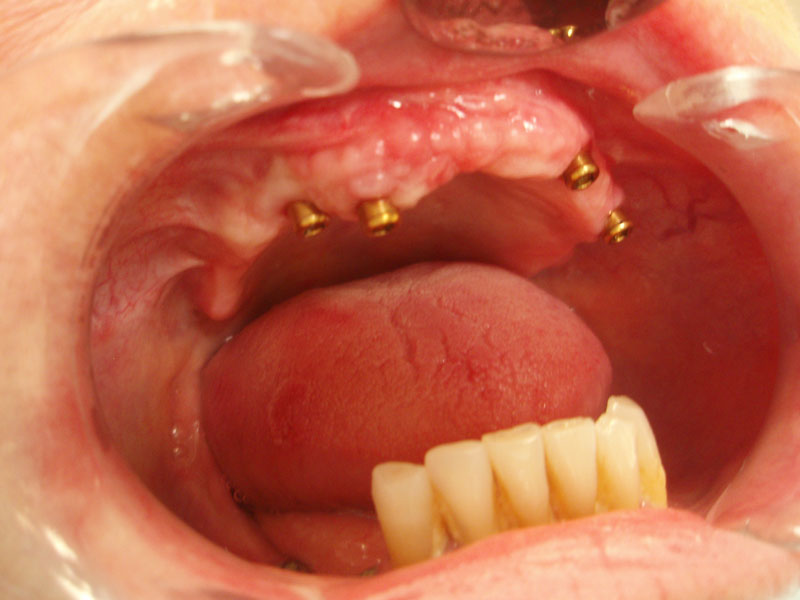

U suradnji sa specijalistom oralne kirurgije vršimo manje kirurške zahvate kao što su: apikotomija ili resekcija zuba (odstranjenje vrha korijena zuba), alveotomija (kirurško vađenje zuba), remodelacija zubnog grebena radi potrebe nošenja zubne proteze, vađenje krivo položenih umnjaka itd.